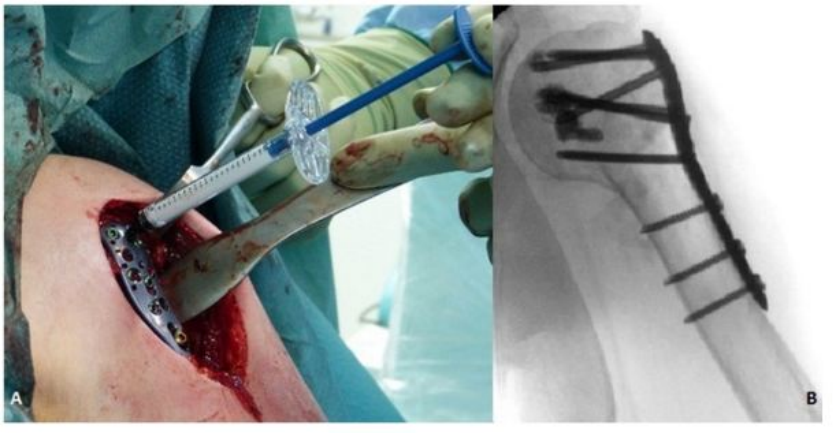

3.骨水泥强化技术

丙烯酸骨水泥在骨科手术中发挥着重要作用,其中聚甲基丙烯酸甲酯(PMMA)已从最初的眼科和牙科领域,扩展至骨科领域,并广泛地应用于假体内植物的固定、肿瘤和椎体骨折的治疗。骨质疏松性股骨近端骨折使用骨水泥强化的内固定系统可以减少约50%的失败率,主要适应症是不稳定型脆性骨折[24]。对骨科医生来说,骨量减少的肱骨近端骨折患者的治疗充满挑战。尽管内植物的设计不断改良螺钉或螺旋刀片在肱骨近端松质内的把持力仍然不足,而这也是内固定失败最主要的原因之一。骨水泥强化技术即将骨水泥注入肱骨头内,填补了内植物与肱骨头之间的空隙,从而增强内植物的把持力[25]。近年来,采用中空的螺钉结合角度稳定钢板系统,骨水泥可以通过中空的螺钉注入,达到骨水泥强化的效果[25]。骨质疏松性胫骨平台骨折与髋部骨折、肱骨近端骨折都不同,它是由于垂直应力直接作用于骨量减少的软骨下骨组织,造成关节面的凹陷和/或劈裂;其经典手术方式是通过植入自体或异体松质骨,支撑重建关节面[26]。但是,自体或异体松质骨在骨折愈合阶段,无法提供足够的力学支撑,造成关节面塌陷利用骨水泥强化技术可能改善上述情况。